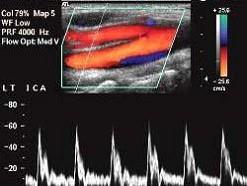

问题 如图所示,该频谱为下列那支血管的频谱特点?(?)

选项 A.颈外动脉 B.颈内动脉 C.颈总动脉 D.颈内静脉 E.椎动脉

答案 A